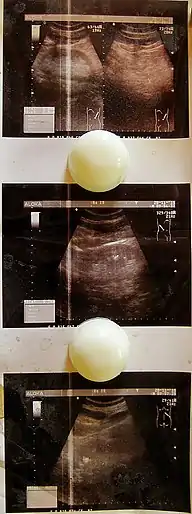

- УЗИ мочеполовых органов, позволяющее исключить сопутствующие заболевания;